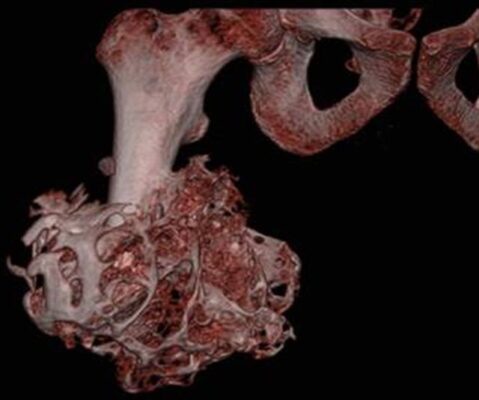

- Chụp cắt lớp vi tính (CT): hình ảnh cho hình ảnh rõ hơn X quang thường, và có ích để lập kế hoạch phẫu thuật cắt bỏ.